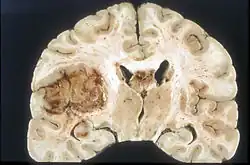

Glioma

Glioblastoma